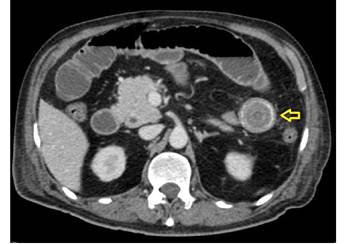

Fuente: examen del paciente realizado en centro de diagnóstico por imágen extrainstitucional

Figura 3. Tomografía axial computarizada de abdomen con contraste (corte axial) que evidencia presencia de cálculo a nivel de yeyuno (flecha).

En dicha institución se revalora al paciente, evidenciando al examen físico mal estado general, consciente, orientado, con signos de dificultad respiratoria y desaturación al aire ambiente hasta 70%, saturación hasta 92% con oxígeno por máscara con reservorio a 8 l/min, piel y mucosas moderadamente secas, normocoloreadas, pulmones con murmullo vesicular disminuido con estertores y roncus diseminados en ambos campos pulmonares, abdomen levemente distendido, con ruidos hidroaereos (+) hipoactivos, blando, doloroso a la palpación profunda en mesogastrio, sin datos de irritación peritoneal, tacto rectal con esfínter normotónico, ampolla rectal vacía y dedo de guante explorador limpio, siendo el resto del examen conservado. Se obtienen estudios complementarios de laboratorios en sangre que reportan: leucocitosis de 10 640/ml, con neutrofilia del 88 %, Hb 12 g/ dl (previo de 15,2), normocítica, normocrómica, Hto 34,8 %, hipoproteinemia con hipoalbuminemia severa con proteínas totales de 4,2 g/dl y albumina de 2,1 g/dl, e hipokalemia leve con K de 3,0 mEq/L, además de gasometría arterial que evidenciaba alcalosis metabólica parcialmente compensada con acidosis respiratoria, con insuficiencia respiratoria aguda hipoxémica moderada (PaFiO2 170), y resto de laboratorios del hemograma, coagulograma, glicemia, pruebas renales y hepatograma dentro de parámetros normales. Se obtiene a la vez Rx de tórax PA y abdomen AP de pie, evidenciando en el primero imágenes radiopacas de infiltrado alveolo-intersticial diseminadas en ambos campos pulmonares a predominio del lado izquierdo, y en la segunda, asas de intestino delgado dilatadas con imagen sugestiva de pila de monedas y niveles hidroaéreos a predominio del lado izquierdo (Figura 1). Tras la obtención de estos exámenes y en el contexto del paciente se han tomado en cuenta los diagnósticos diferenciales de obstrucción intestinal vs hemorragia digestiva alta, este último según la institución inicial que realizó la referencia, que indicaba la presencia de vómitos porráceos y el evidente descenso de la Hb en 3 puntos, por lo que se continúa con la indicación de endoscopia digestiva alta la cual reporta: “Datos de obstrucción intestinal alta (debito de retención proveniente de segunda y tercera porción duodenal) (Figura 2), sospecha de metaplasia columnar de esófago, gastritis crónica superficial de antro, estudio parcialmente satisfactorio (por segmentos con debito retentivo no valorables)”. Con estos hallazgos se refuerza mucho más la primera hipótesis, pero llama la atención que un paciente sin antecedentes quirúrgicos abdominales presente datos de obstrucción intestinal, además de tratarse de un paciente con un cuadro clínico atípico, y que al momento no había podido ser resuelto bajo medidas conservadoras, por lo que se decide solicitar estudios ampliados extrainstitucionales, como una tomografía axial computarizada (TAC) de abdomen con contraste de forma urgente; tras gestionar la misma, se obtiene reporte que indica (Figuras 3y4): “Hallazgos tomográficos compatibles con íleo biliar (imagen de cálculo de 4 x 3,2 cm con áreas de calcificación en su pared a nivel de yeyuno proximal), probable fístula bilio-digestiva (colecistoduodenal), neumobilia, pequeños quistes renales simples bilaterales, hallazgos de la porción valorable de tórax sugerente de proceso infeccioso de etiología viral sugestivas de COVID-19”. Con ello se solicita la valoración por el servicio de cirugía que, en misma fecha de ingreso, realiza procedimiento quirúrgico de laparotomía exploradora, enterotomía, extracción de cálculo y enterorrafia, con diagnóstico postoperatorio de “Obstrucción intestinal alta, íleo biliar, neumonía por SARS-COV2, hiperplasia prostática”, describiendo en los hallazgos operatorios un cálculo de aproximadamente 4 x 4 cm que ocupaba la totalidad de la luz yeyunal a +/- 60 cm del ángulo de Treitz.